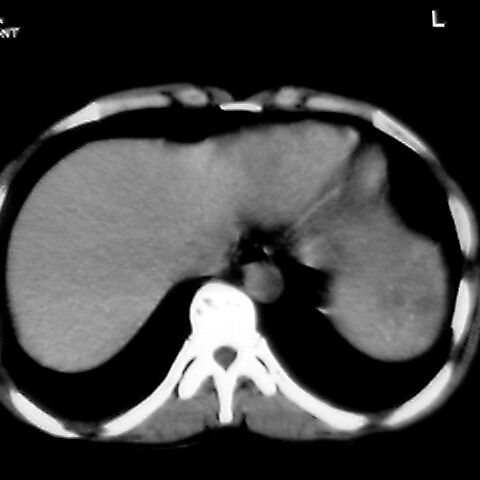

女 48岁 食道癌术前体检发现脾占位。

考虑脾脏血管瘤,中央低密度为血栓形成

脾脏低密度灶伴钙化,增强化明显,中心见液化坏死灶,强化延时明显。考虑血管瘤。转移瘤待排。

转移瘤不可能单发,考虑脾血管瘤。